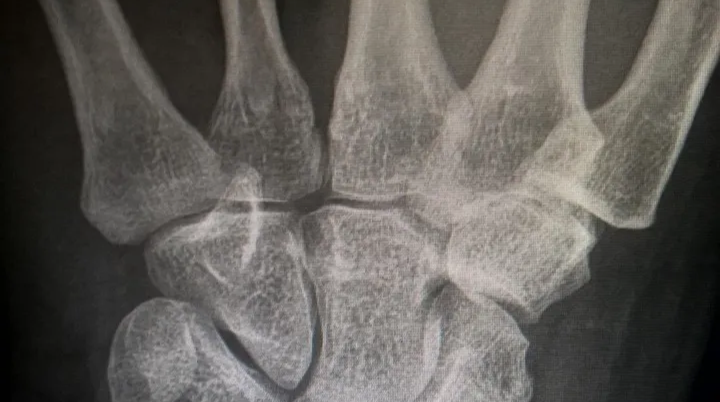

콘드로이친(Chondroitin)은 우리 몸의 연골과 결합조직 속에 자연적으로 존재하는 성분으로

관절 사이에서 충격을 흡수하고 마찰을 줄여주는 역할을 합니다.

나이가 들면서 콘드로이친이 점점 감소하면 관절이 뻣뻣해지고 통증이 생길 수 있다고 합니다.

콘드로이친 효능 2 – 연골 보호 및 재생 도움

콘드로이친은 단순히 통증을 완화하는 것에 그치지 않고,

-연골 세포의 손상을 줄이고 재생을 돕는 역할도 합니다.-

부모님은 예전보다 무릎에서 ‘뻣뻣함’이 줄었다고 하셨는데,

이게 바로 콘드로이친 효능 덕분이라고 생각합니다.

콘드로이친 효능 3 – 관절 윤활 및 유연성 개선

콘드로이친은 관절 속의 윤활 작용을 촉진해 마찰을 줄여주는 역할을 합니다.

실제로 콘드로이친은 관절액의 점도를 높여 유연성을 개선하는 효과가 있다고 합니다.